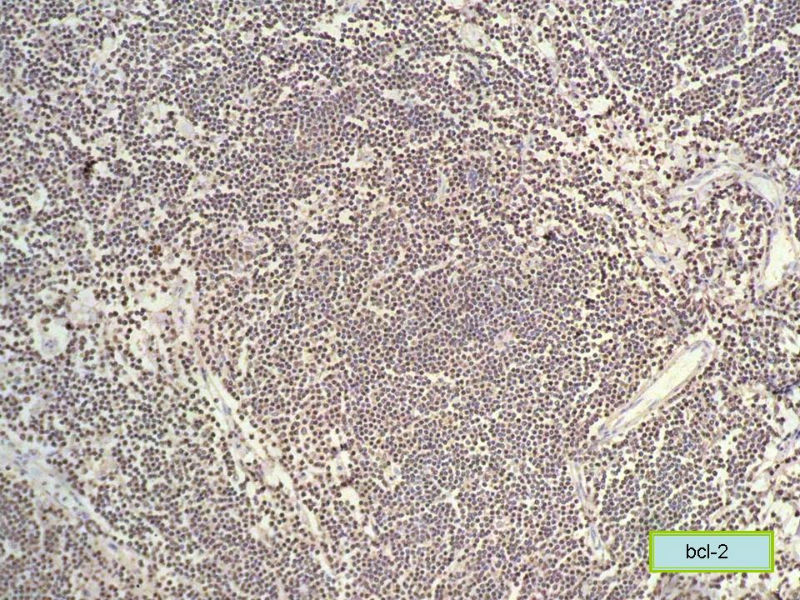

请再标记CD20和CD79a!图片中阳性不明确,根据T细胞标记看,应该是B细胞结节。Ki67散而少,不支持低级别滤泡性淋巴瘤,若B细胞弥漫阳性,则是惰性B细胞非霍奇金淋巴瘤,首先考虑套细胞,然后是边缘区淋巴瘤。不做生发中心标记,Bcl-2在小B细胞淋巴瘤分类中无意义。

CD20(+),Kappa(+),ki-67(+)>2%,Lambda(+),Pax-5(+),符合粘膜相关淋巴瘤。